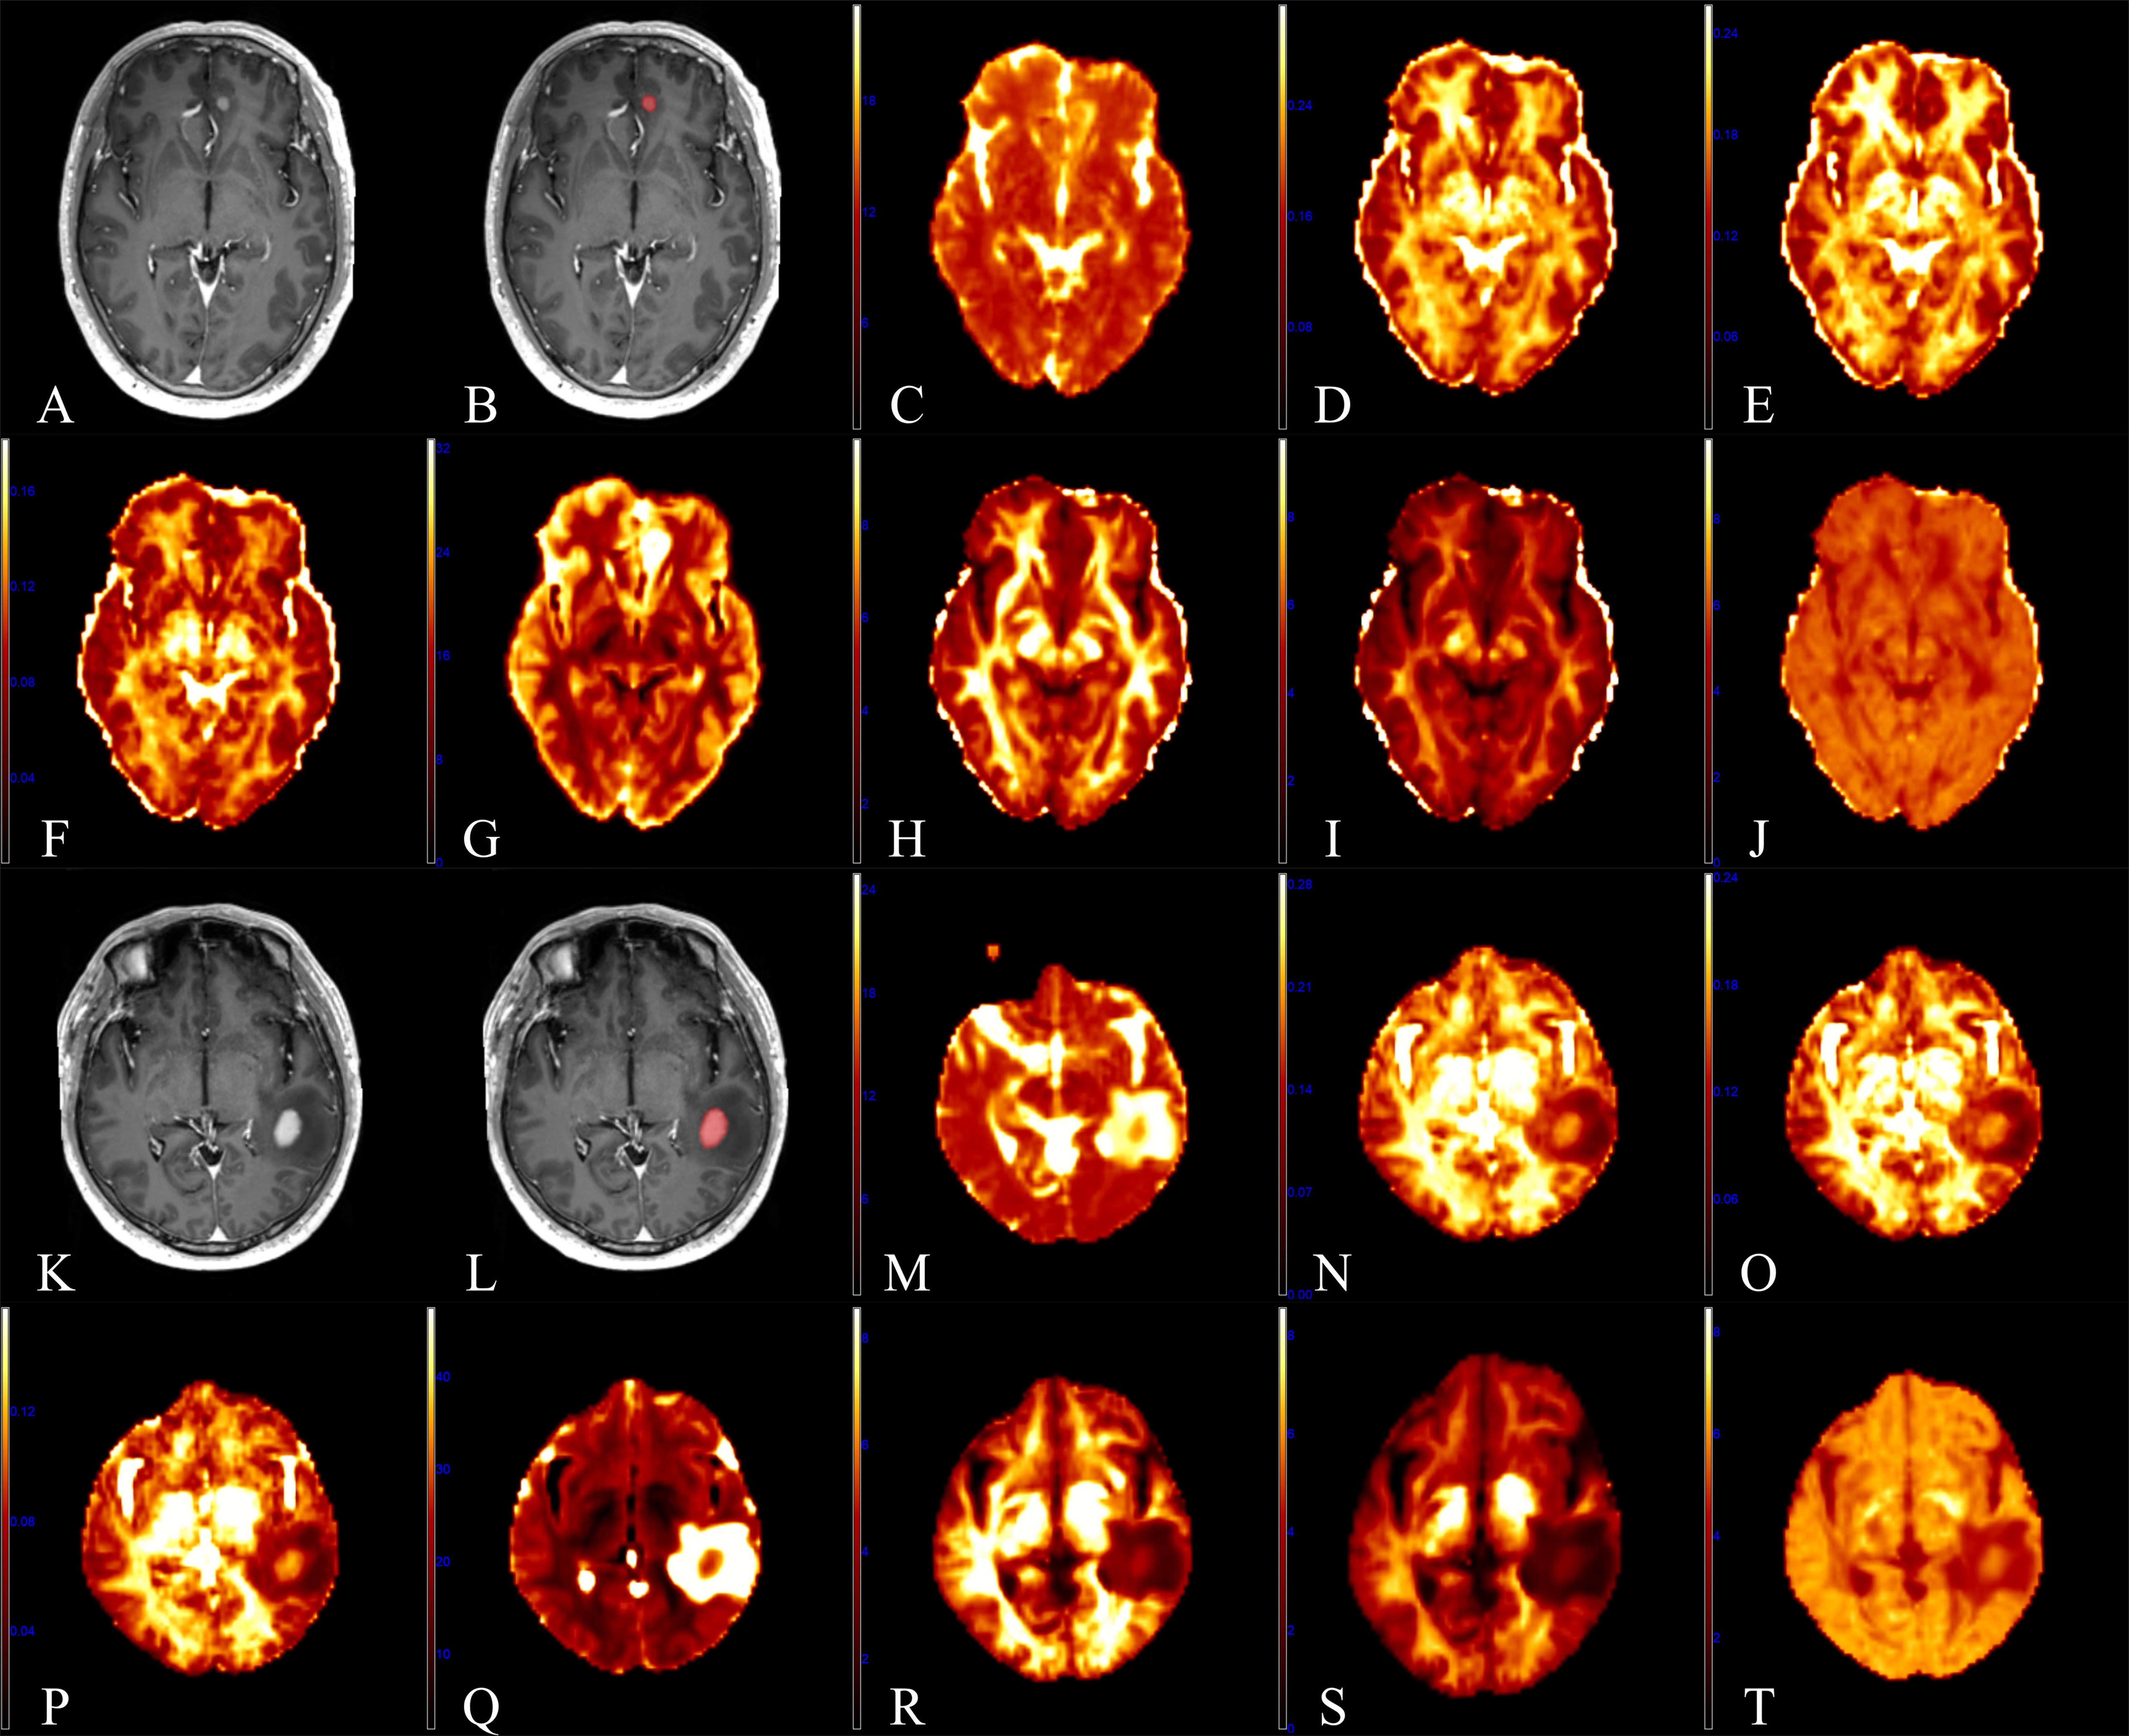

Fig. 2 (A) The receiver operating characteristic (ROC) curves of the mean apparent propagator (MAP) parameter values in the contrast-enhanced area. (B) The ROC curve of q-space inverse variance (QIV) in the contrast-enhanced area.

As shown in Table 1, the mean values of RTOP, RTAP, RTPP, NG, NGAx, and NGRad in atypical HGG group were significantly lower than those in PCNSL group (P<0.05), while QIV significantly higher in atypical HGG group. MSD had no significant difference between two groups (p=0.0630.05). The ROC analyses of MAP parameters with significance are shown in Table 2 and Figure 2.

In this study, the diagnostic efficiency of MAP in discriminating between atypical HGG and PCNSL was explored. Our results demonstrated that the MAP-MRI did well in differentiating atypical HGG from PCNSL. Among all significant parameters, NGRad achieved the highest area under the curve (AUC). According to previous studies, the cellularity and mean nucleus/cytoplasm ratio of lymphoma is higher than that of glioblastoma, which was identified by our results with significantly higher NG, NGAx and NGRad in PCNSL. Pang et. al [6, 7] showed lower MD in PCNSL compared to HGG using DKI. In addition, researchers showed that the water diffusivity in tissue is mainly affected by the extracellular space. Lower MD in PCNSL than that in HGG demonstrated that the PCNSL has smaller extracellular space than HGG. In our research, significantly higher RTOP, RTAP and RTPP were obtained in PCNSL, which was in accordance with the findings of Pang et al [6, 7].